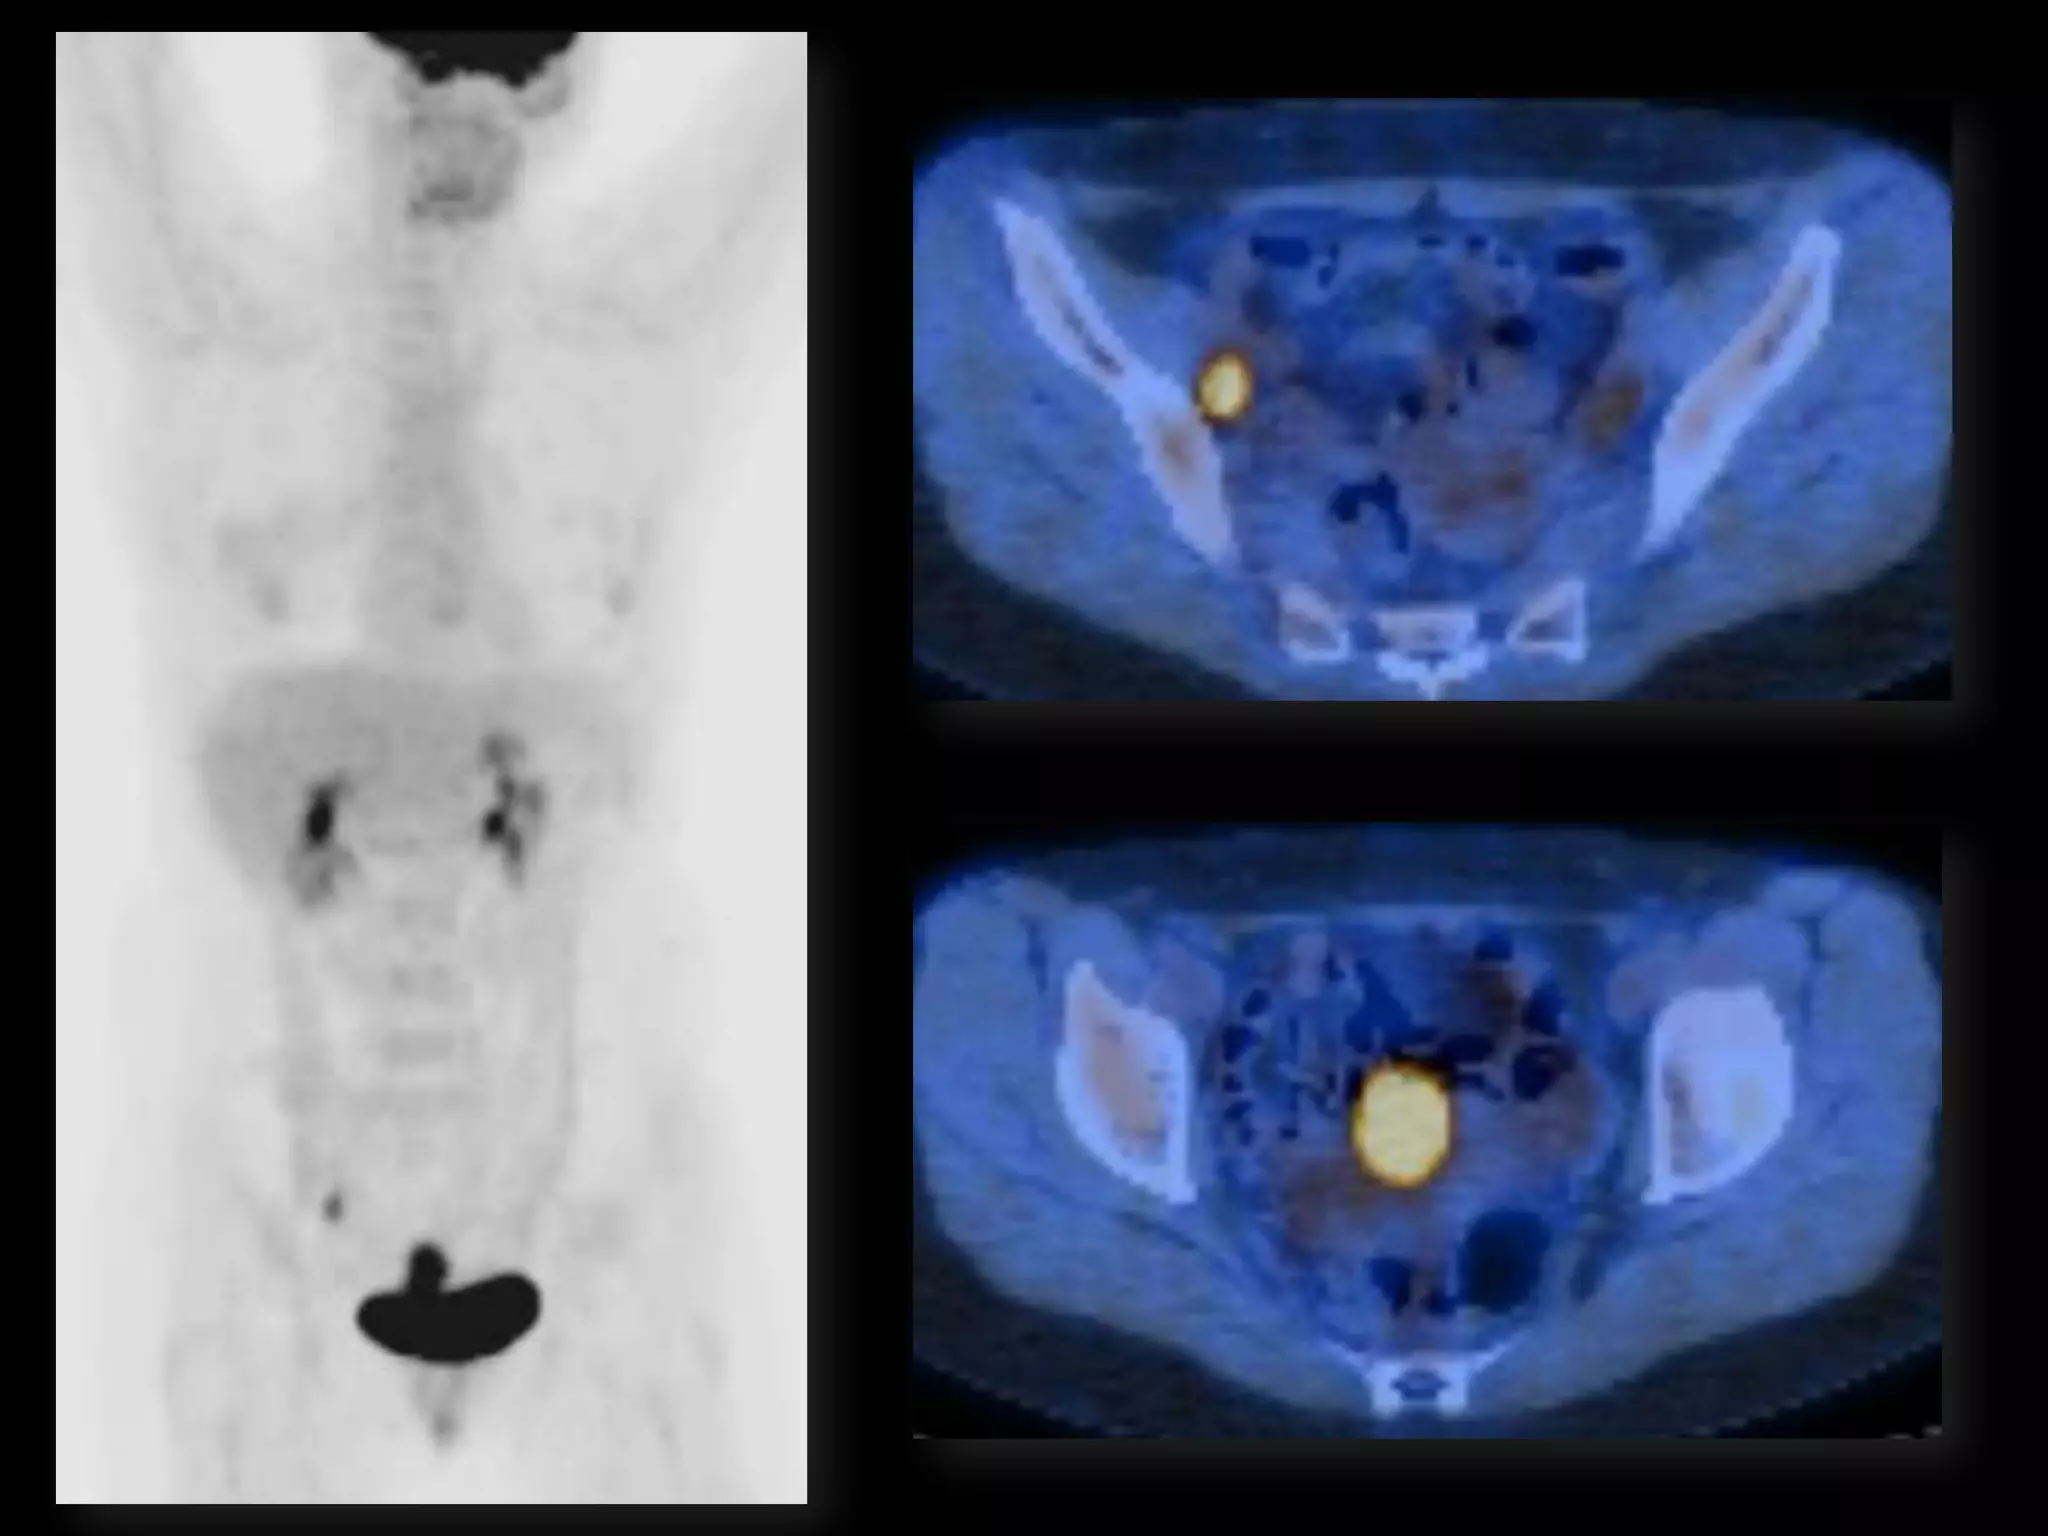

MRI findings - Stage IIB

with PET/CT - Stage IIIB

HISTORY โ€ข 42 yo female โ€ข Recent immigrant from China โ€ข C/O postcoital and intermenstrual bleeding โ€ข Abnormal GYN exam โ€ข Abnormal biopsy โ€ข Further imaging performed

MRI findings -Stage IIB with PET/CT - Stage IIIB Cervical Cancer

Role of MRImaging in Tx Stratification of GYN (Cervical) Cancer โ€ข Cervical Cancer โ€“ 2nd most common ca in women worldwide โ€“ Developing countries; pk 30-40 yrs โ€ข FIGO classification โ€“ revised in 2009 from just clinical to incorporate cross-sectional imaging (CT, MR) โ€ข Staging accuracy of MR 85-96% โ€“ Best test to assess tumor size and location; invasion into parametria, pelvic side wall, adjacent organs; local nodal enlgment โ€ข PET/CT helpful in staging advanced disease โ€“ Demonstrates unexpected sites beyond pelvis โ€ข Treatment options โ€“ Radical surgery - early stage (IA, IB1, IIA1) โ€“ Primary Chemo and Radiation โ€“ bulky IB2 or IIA2, or local advanced (IIB or greater) Sala et al. Radiology 2013; 266: 717.